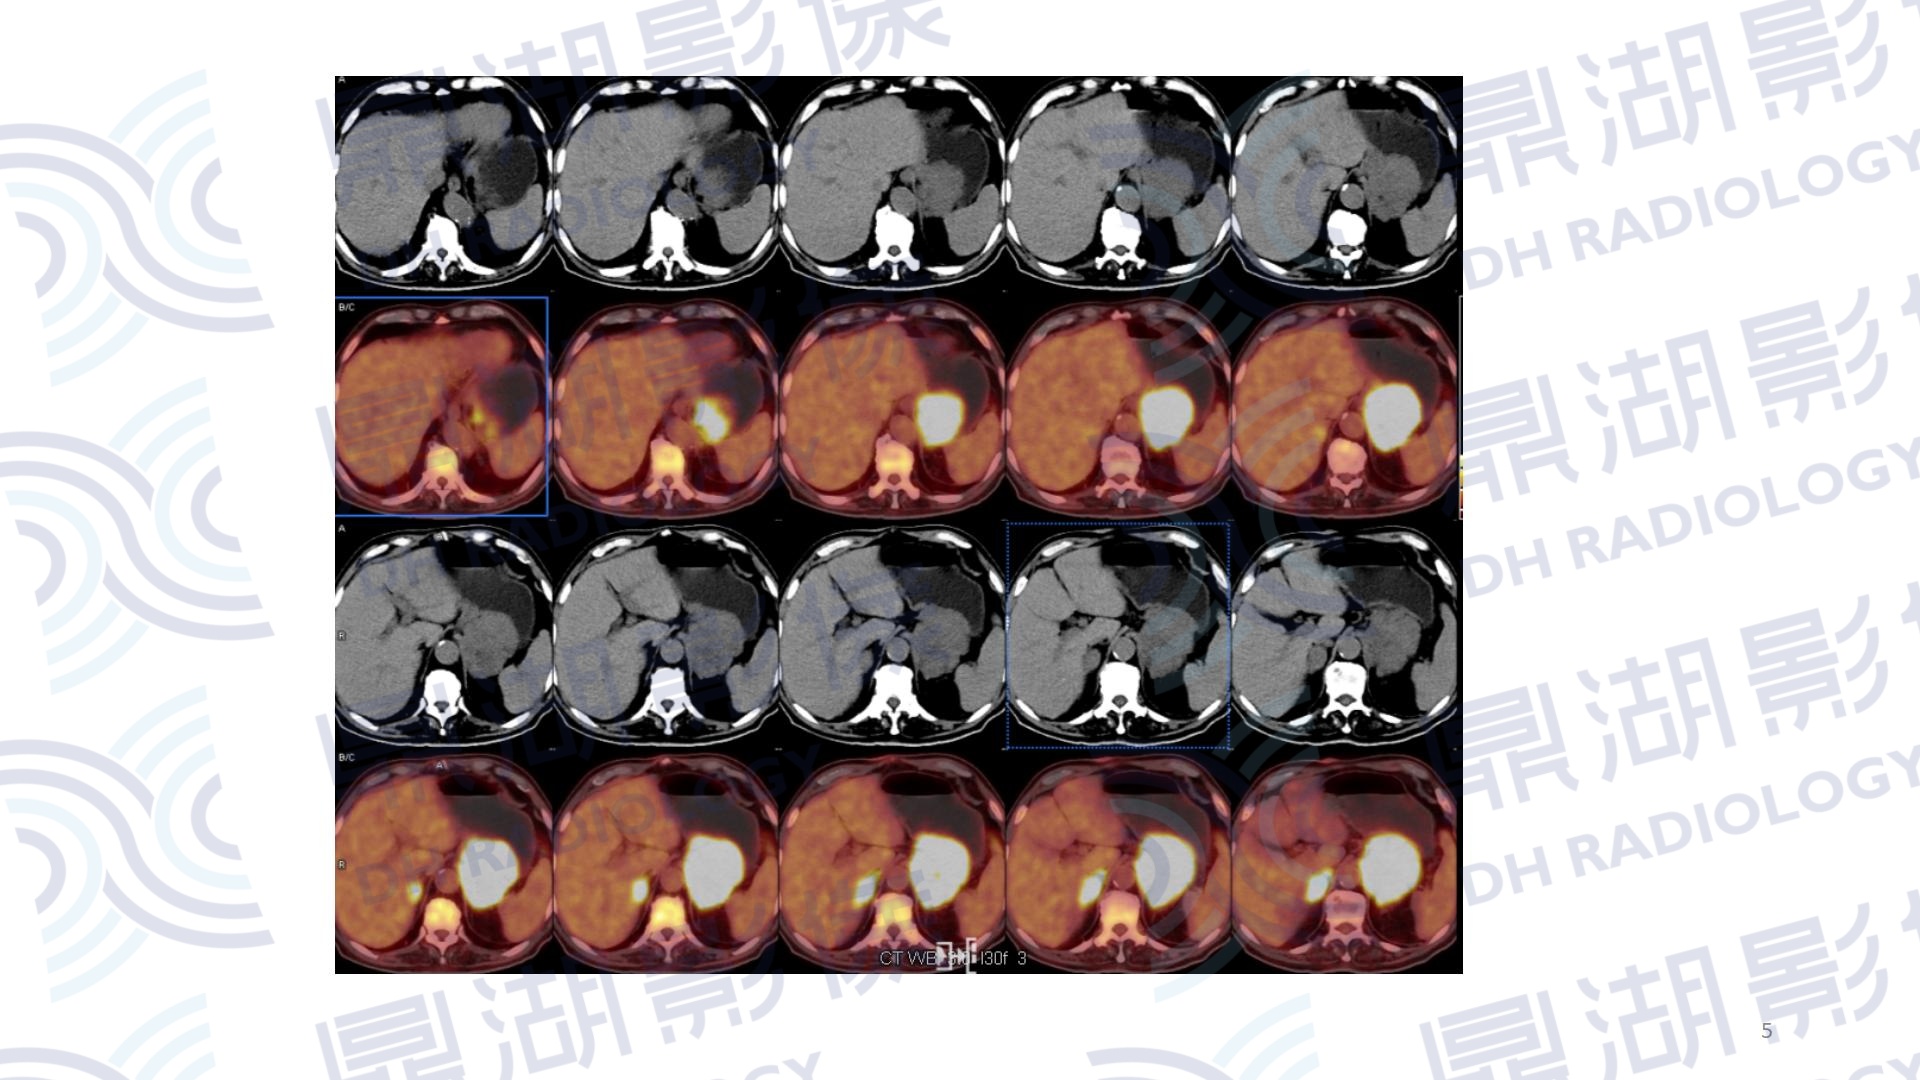

患者,女性,80岁

主诉:左侧肢体无力2周

现病史:患者两周前发现无明显诱因左侧肢体无力、行走不稳伴发热,表现为走路向左侧偏斜,无恶心呕吐,一直未予以治疗。

既往史:无高血压、糖尿病病史;无传染病病史

查体:无明显异常